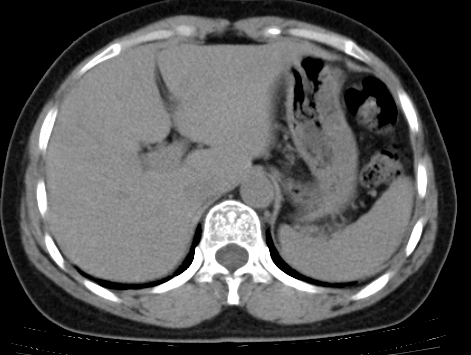

标题: CT25227:背部疼痛伴双侧胸壁痛2月,食欲差。 [打印本页]

标题: CT25227:背部疼痛伴双侧胸壁痛2月,食欲差。

肺结核并胸椎结核?请各位高手指教。

用椎体的条件来扫胸椎呀!考虑1左侧胸膜小结节形成2椎体结核并冷脓肿形成

考虑胸椎结核并椎旁软组织肿胀。

左肺结核灶,胸椎结核并冷脓肿。

支持!不排除骨原发淋巴瘤肺内转移。

左肺结核灶,胸椎结核并冷脓肿